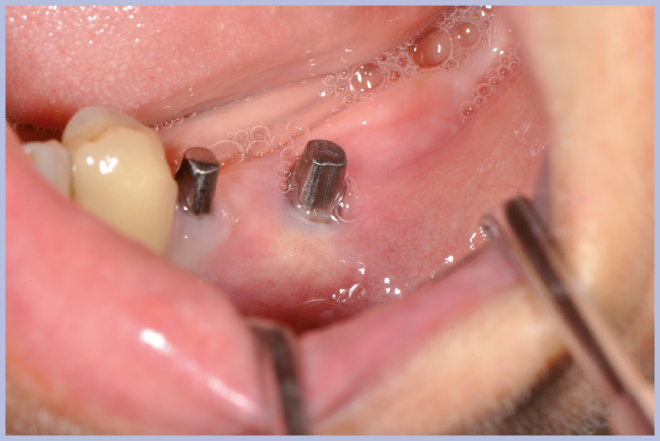

Dopo 3 mesi si esegue il rientro chirurgico con tecnica flapless per il posizionamento dei tappi di guarigione transmucosi, utilizzando la stessa mascherina chirurgica senza le boccole per guidare il percorso dei mucotomi (Figg. 31-36).

- Figg. 31-35 – Al momento della riapertura utilizzo della guida chirurgica per l’esposizione implantare

- Fig. 32